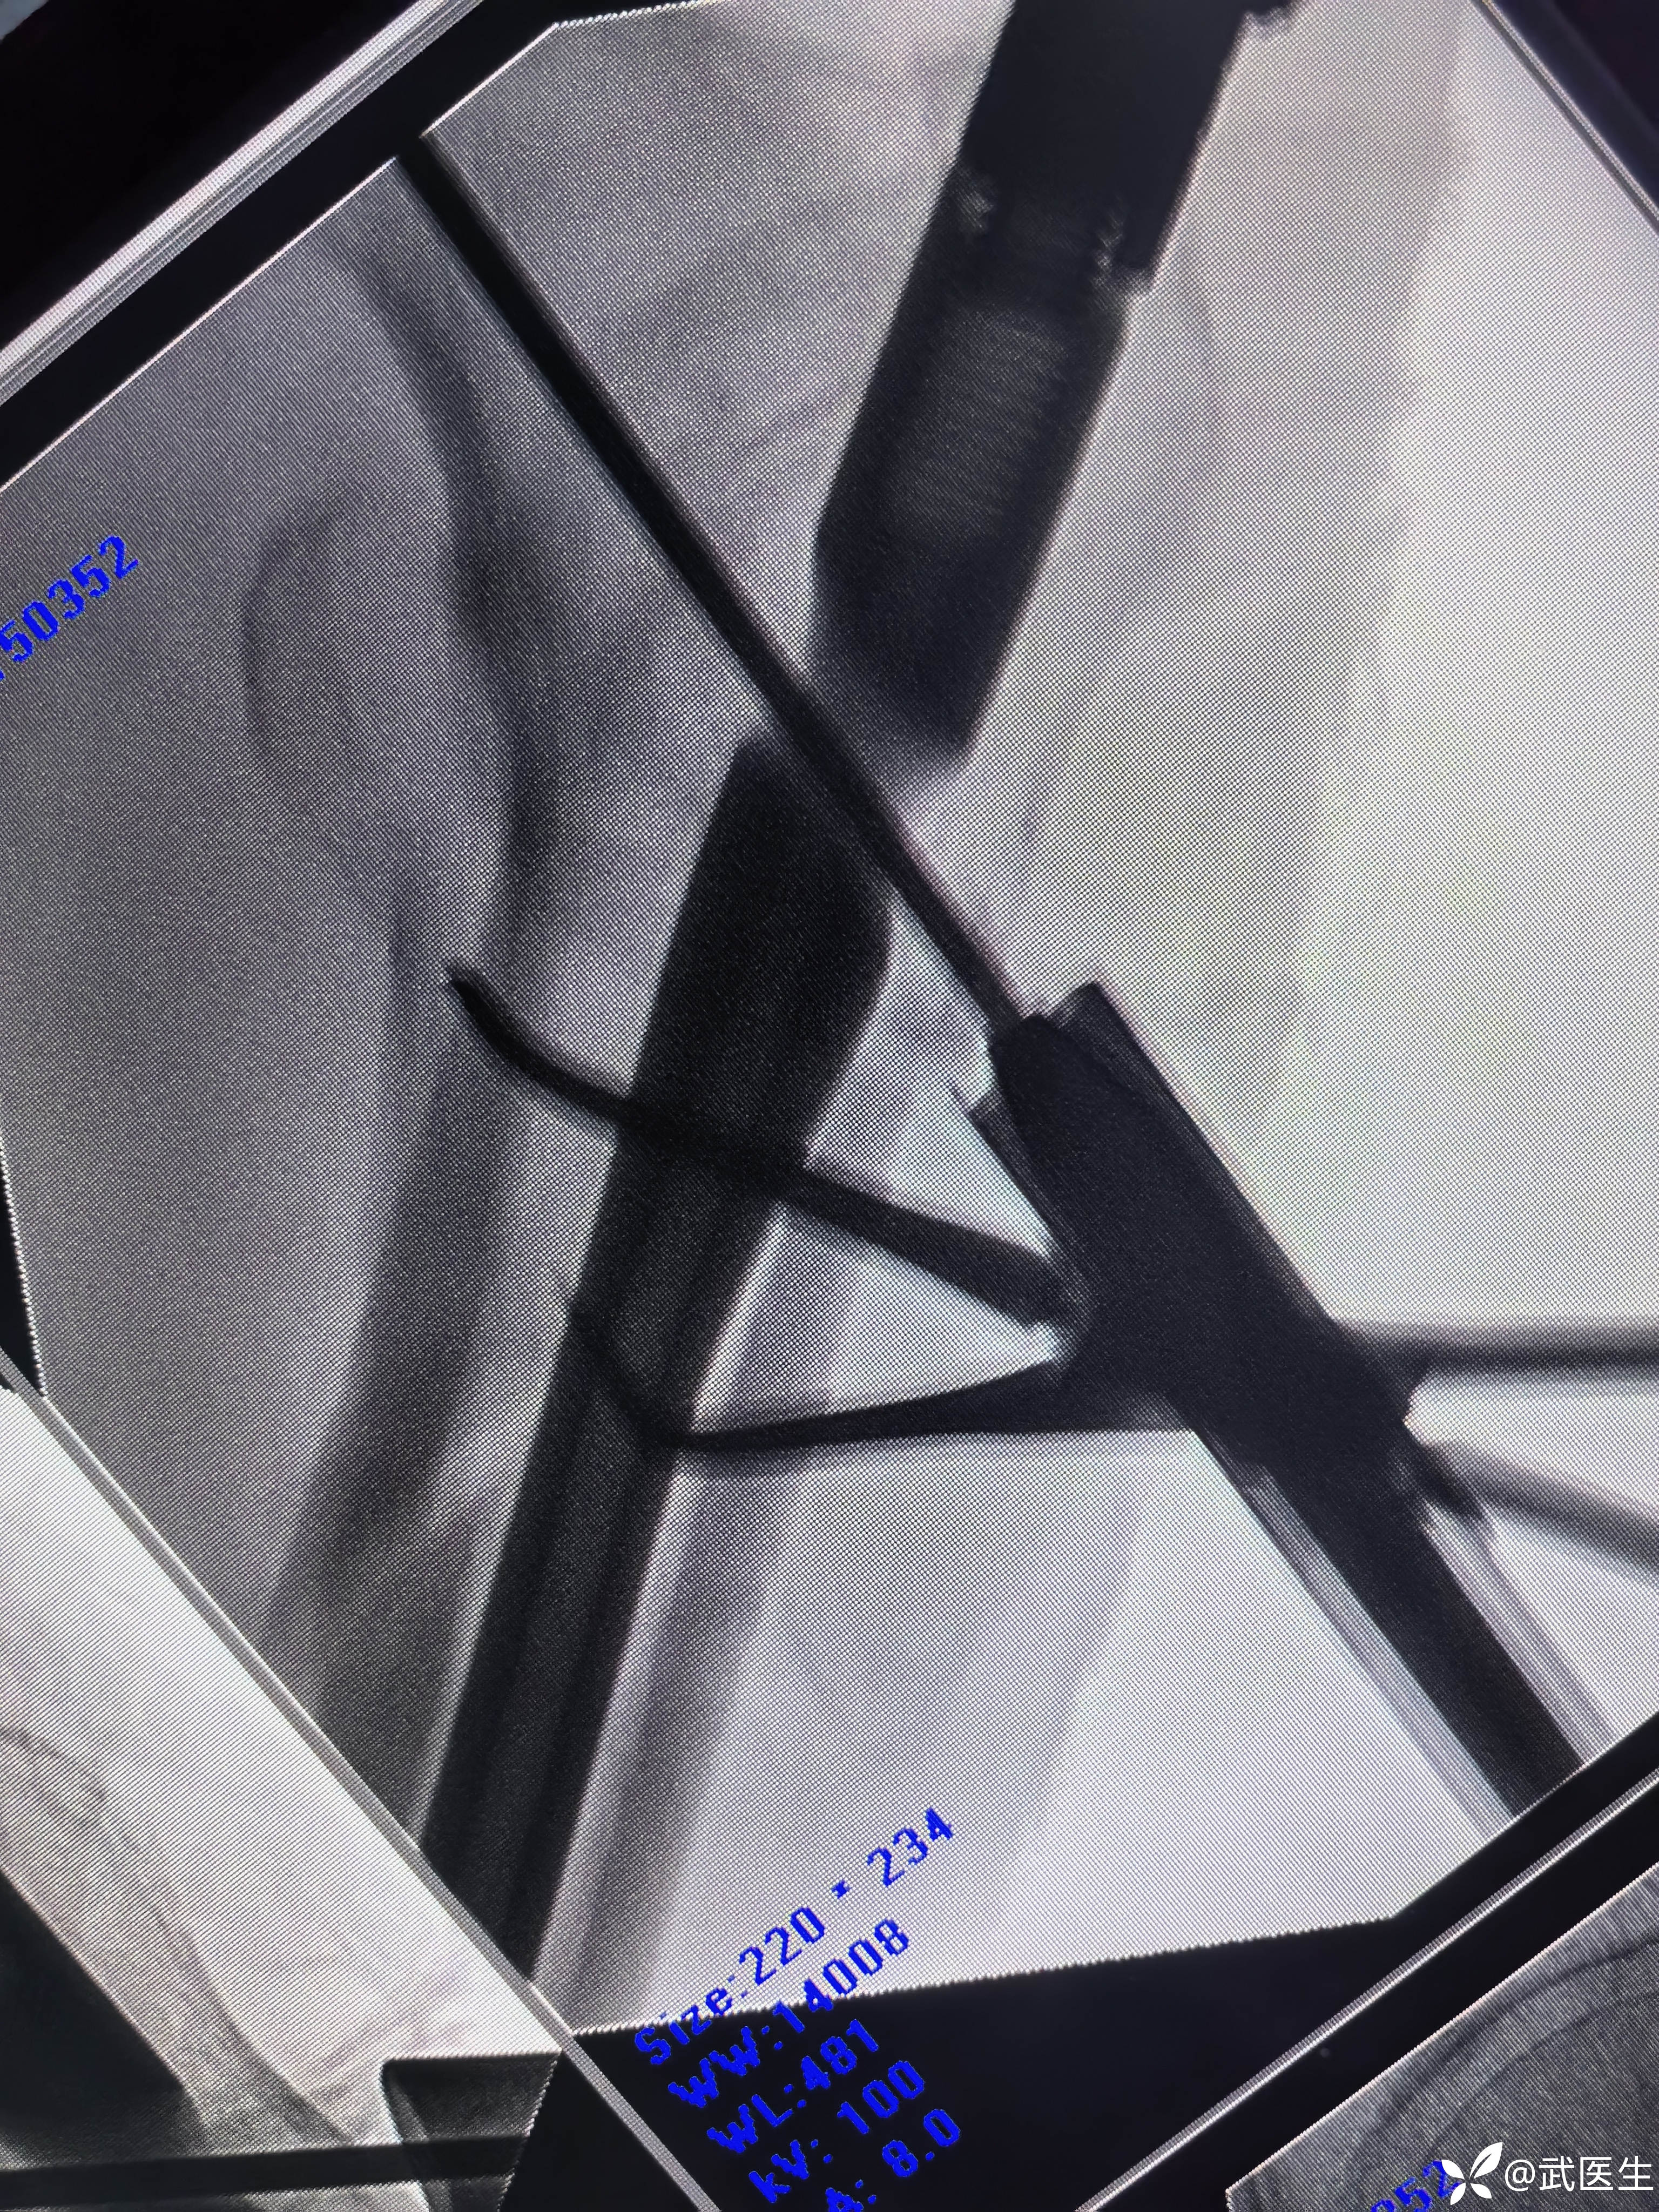

开口后置入金手指,找股骨远端

找不到,从头颈钉处切口,置入髌骨复位钳辅助复位,顺利置入导针,骨折对位满意